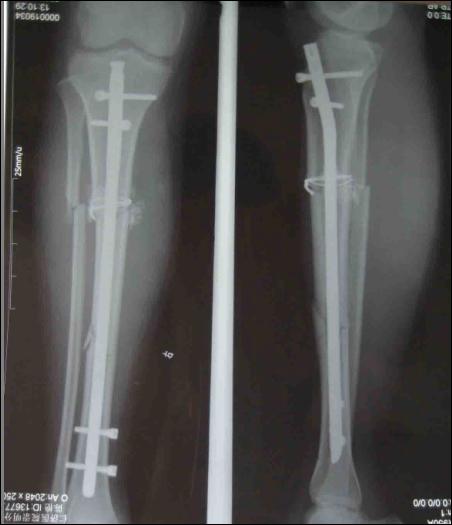

被打入鋼釘?shù)氖疽鈭D